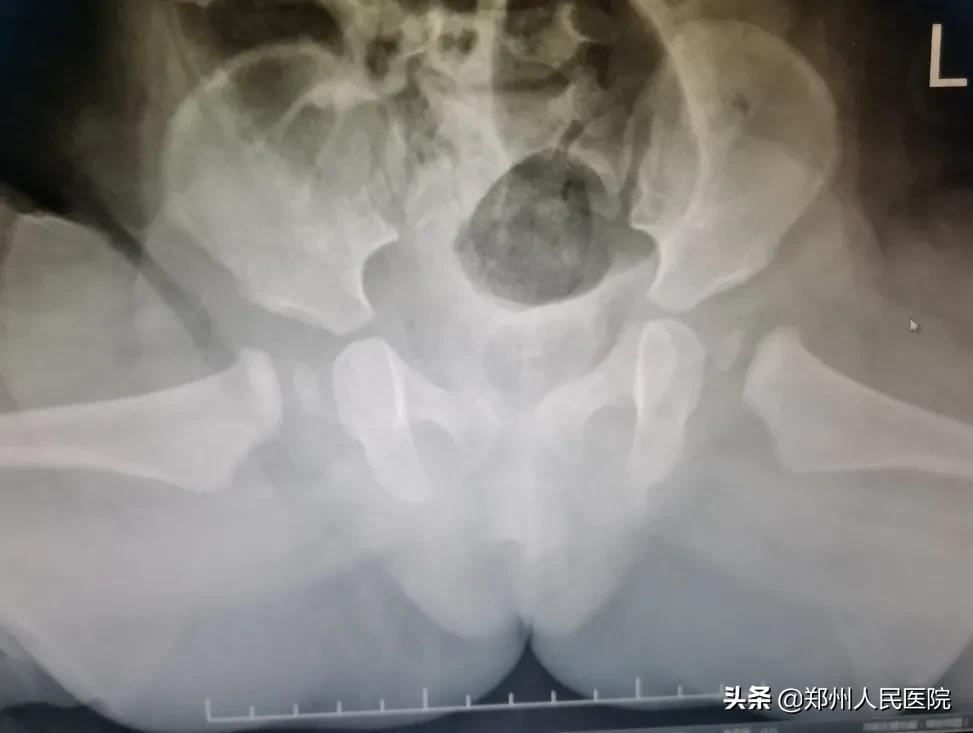

来院后,经过体格检查、走路姿势观察、X光片等,确诊了睿睿也是发育性髋关节发育不良,但是由于错过了最佳治疗时机,孩子只能做截骨手术。

术后

←术后固定

原来通过截骨矫形,把发育不正的髋臼给它矫正到正常位置上来,这样就避免了进一步异常损害。如果任其发展不干预,孩子可能会终生残疾!

“该年龄段的患儿髋关节已开始受力,脱位程度多已加重,骨与软组织的继发改变加剧,保守治疗较难,多采用手术治疗。须通过一系列骨盆和或股骨截骨手术和软组织松解手术,把股骨头安全置入髋臼内,术后联合石膏固定、功能锻炼治疗,能取得比较理想的效果。”骨科三病区副主任医师张保龙说。